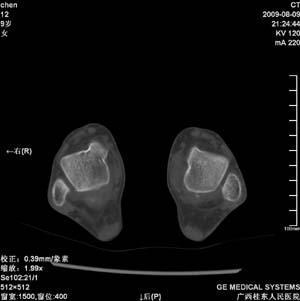

标题: PED2867:右侧内踝肿胀,骨质改变,请各位老师会诊 [打印本页]

标题: PED2867:右侧内踝肿胀,骨质改变,请各位老师会诊

九岁小朋友,近期左侧内踝疼痛,局部肿胀,平时无特殊,近期经常溜干冰

对不起,是右侧内踝肿胀

双踝关节骨质及发育未见异常。

左侧内踝密度增高,请结合临床!